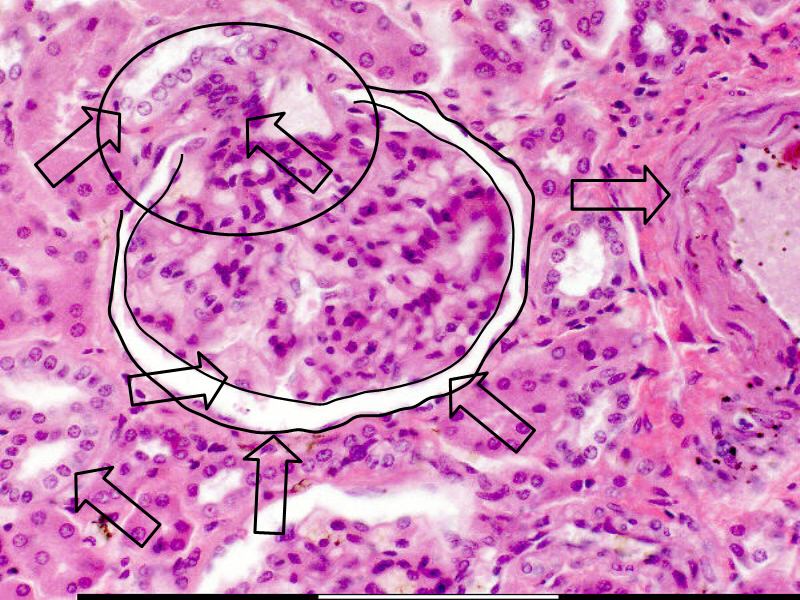

What are the clinical implications of the histological morphology?

Traumatic events in the liver

Illustrate the damaged area of Liver acinus

Visible histologically

Caused By Various Agents / Diseases

• Describe the mechanism

• Identify and explain the area

• Indicate zones of damage on a sketch

• Correlate with slide